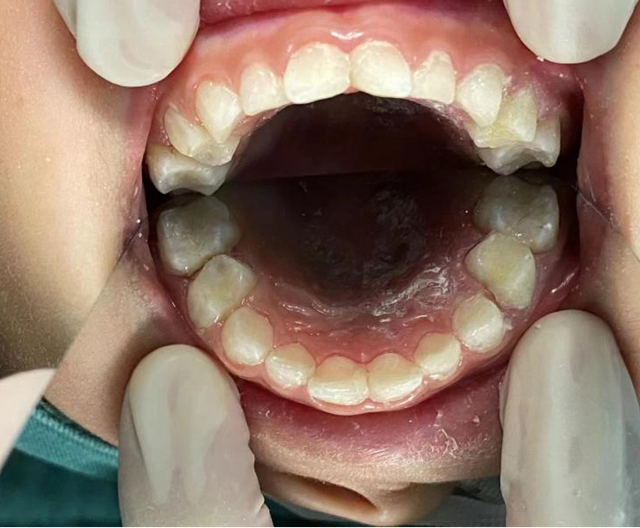

我们经常遇到小朋友不配合的情况,全麻下舒适化儿童口腔治疗,就是针对这类不配合又有许多坏牙齿小朋友的最佳选择,可以舒适化地一次性解决小朋友口腔问题。

首先患儿坏牙多,就诊次数多,增加了就诊成本;其次许多口腔问题需要局麻伴有疼痛,患儿不配合还容易对口腔治疗产生阴影,例如根管治疗、拔除难度较大的牙、唇舌系带修整术等,这时全麻下舒适化口腔治疗就是最佳的选择。

在全麻下可以安全、高效地一次性完成儿童口腔内所有患牙的治疗,解除患儿的焦虑和疼痛,节省了患儿家长的时间,减少就诊次数,提高了诊疗效率。

对于低龄及看牙恐惧的宝宝们,通过该项技术,绝大多数能够实现全口患牙的治疗。手术后通过儿童口腔门诊的随诊及口腔卫生习惯的养成,可以达到满意的治疗及愈后。